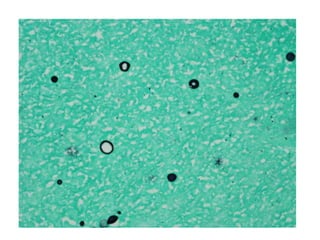

• #34 Cryptococci in perivascular space

• #35 Mucicarmine

• #36 Alcian Blue

• #37 PAS

• #38 Mucicrmine stain

• #39 CNS